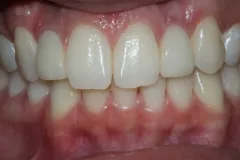

Caso 5

Se realizan Coronas dentales en Ziconio para mayor resistencia,mejorar armonia y estética, en piezas con resinas desajustadas y caries recidivas.